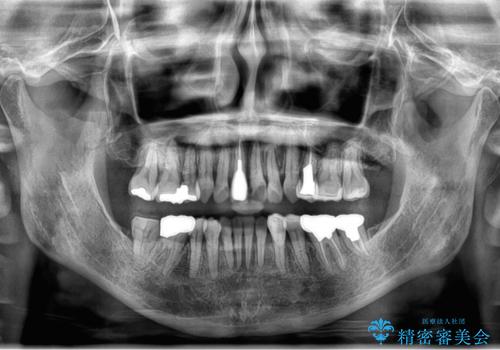

50代女性 八重歯を矯正治療 歯並びの中等度のがたつき

- 八重歯の矯正を希望されて来院。

歯は入りきらないため、通常の抜歯矯正を行いました。

歯がご年齢的に動きにくいため、被せ物のやり替えを含めて治療期間の短縮を図りました。

矯正治療自体は2年半、虫歯治療等で1年ほどかかっています。

詰め物や被せ物のやり替えも併せて行っているため、治療期間を比較的短縮できました。